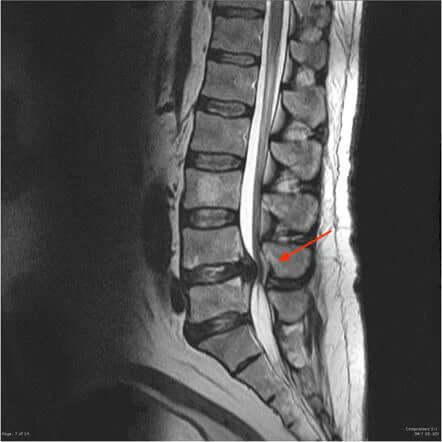

Hier sind die Röntgenaufnahmen der Lendenwirbelsäule einer Person mit Wirbelkompression.

Auf dem Bild links können wir sehen, wie die Wirbel einer Person auf Röntgenstrahlen aussehen, wenn sie zusammengedrückt sind. Auf dem Bild rechts sehen wir hingegen, wie die Wirbel richtig voneinander entfernt aussehen sollten.